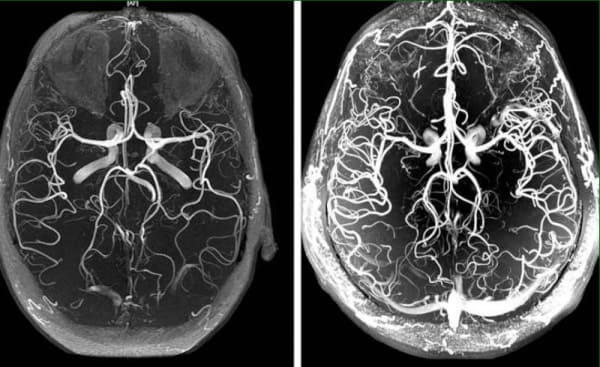

Нарушение на кръвообращението в мозъка — как да разпознаем предстоящата беда и да се предпазим от опасни последици.

Нарушение на кръвообращението в мозъка това е патологично състояние, при което тонусът на кръвоносните съдове и нормалното функциониране на мозъчните тъкани са нарушени. В тази статия можете да прочетете за причините, механизмите и симптомите, при които е време да се задейства алармата. Както и за страховитите усложнения на това коварно заболяване и за съвременния подход към терапията, достъпен за всеки.